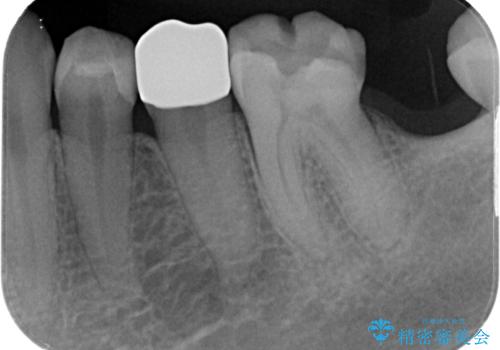

- 詰め物が外れかけているのでやり替えたいとのことで来院された患者様です。来院時に詰め物の不適合を認めたので歯髄診を行い歯髄の生活反応を確認できたので、フルジルコニアクラウン、セラミックインレー修復を行っていくことにしました。

拡大鏡視野下で、コンポジットレジン、虫歯の除去を行い、フルジルコニアクラウン、セラミックインレーに適した形に整えました。

歯と歯茎の間に圧排糸と言われる糸を入れてシリコーン印象材にて精密な型どりをしました。

セラミックインレーの装着時には、唾液の侵入を防ぐために、ラバーダム防湿を行いました。